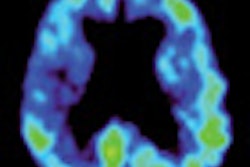

Nuclear medicine firm Zecotek Photonics has received a patent on its technology for enhancing the performance of PET scanning and other medical imaging systems.

The technology utilizes Zecotek's patented scintillation crystals and solid-state photodetectors and optical components integrated with the University of Washington's data acquisition methodologies and image reconstruction algorithms for new scanners.